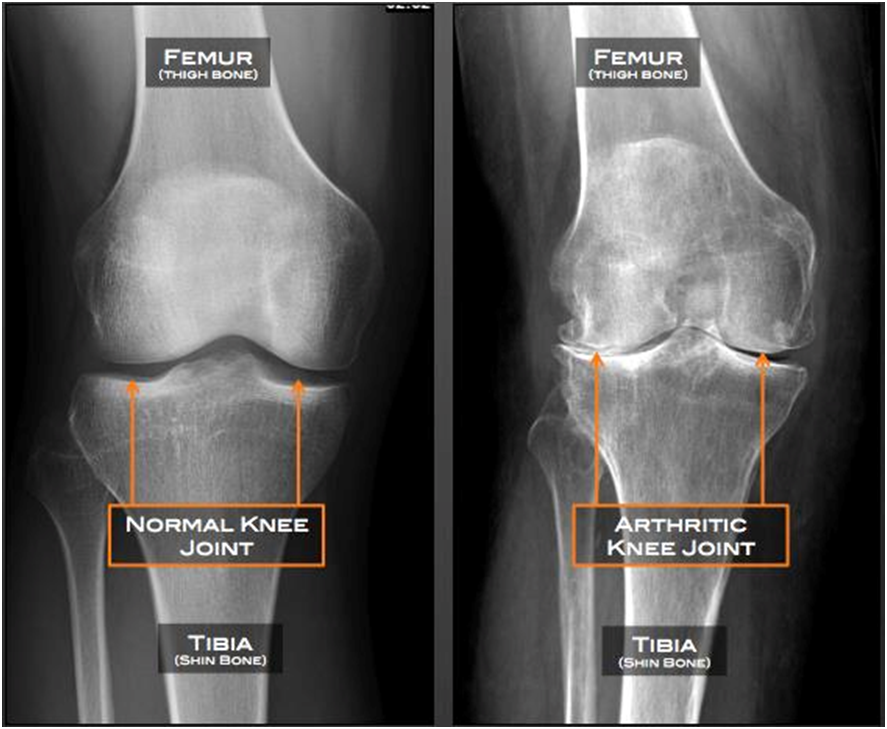

Knee replacement surgery, also known as knee arthroplasty, is a surgical procedure designed to alleviate chronic knee pain and improve joint function in individuals with severe knee damage. The surgery involves replacing the damaged or worn-out surfaces of the knee joint with artificial implants made of metal alloys, high-grade plastics, or polymers. These implants mimic the natural movement of the knee, providing stability and reducing pain.

Additional X-rays of the legs may be needed.